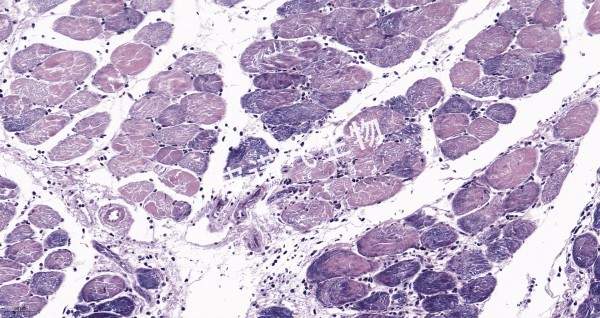

PTAH 肌肉